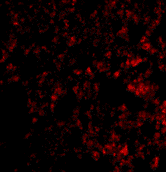

Below: Immunofluorescence of Blimp-1 in mouse lung tissue with Blimp-1 antibody at 20 µg/ml.